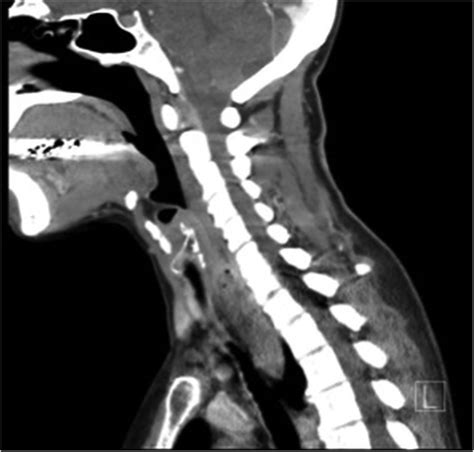

Diagnosing polyps in oesophagus requires a systematic approach. Since these growths rarely cause symptoms until they reach a certain size, doctors rely on imaging and direct visualization. The primary diagnostic tools include:

CT Scan Used for staging or if the mass is suspected to be large or complex.